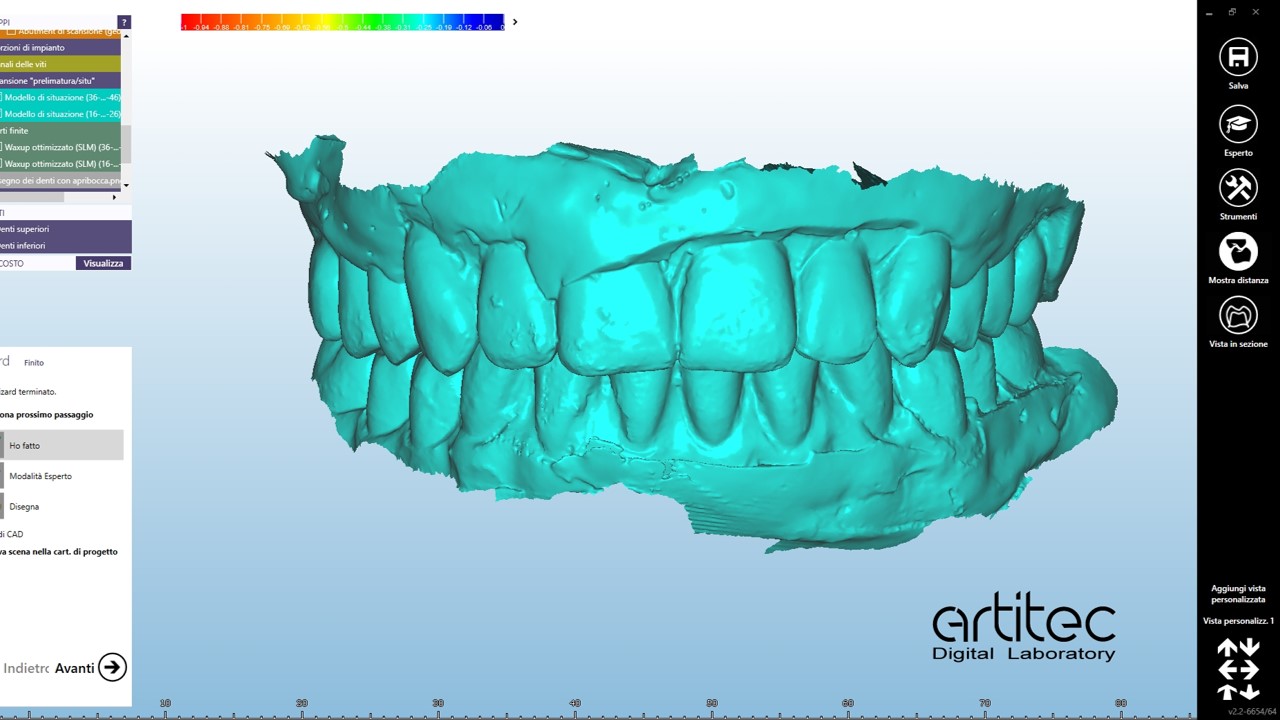

foto 08 scansione in occlusione protesi ribasate

La fase protesica inizia con la ribasatura delle protesi provvisorie per rilevare la corretta anatomia della cresta. Quindi si procede a scansionare con scansione intraorale le impronte ottenute fuori dal cavo orale, poi le protesi provvisorie ribasate ricollocate nel cavo orale e la loro occlusione. Infine, si scansionano le creste edentule dopo aver posizionato gli scan body per tecnica digitale per rilevare la posizione degli impianti. Per la pianificazione sono scattate delle fotografie intraorali ed extraorali per la definizione dei limiti perimetrali del volto al fine di poter eseguire la programmazione del caso tramite il software di previsualizzazione. Le scansioni così ottenute sono poi inviate al laboratorio per la realizzazione di un prototipo delle protesi in prova.

Durante la seconda seduta della fase protesica si provvede alla prova dei prototipi in polimetilmetacrilato (PMMA) avvitati per verificare la linea del sorriso, l’occlusione, la forma

degli elementi dentari e la dimensione verticale. Sebbene già molto precisi i prototipi sono ribasati con silicone morbido per permettere al laboratorio di ottenere un accoppiamento perfetto e la massima aderenza tra mucose e protesi.